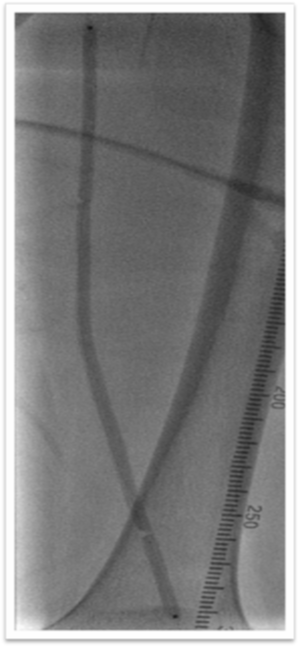

图为:术中造影评估 髂股段

图为:术中造影评估 膝下踝下段